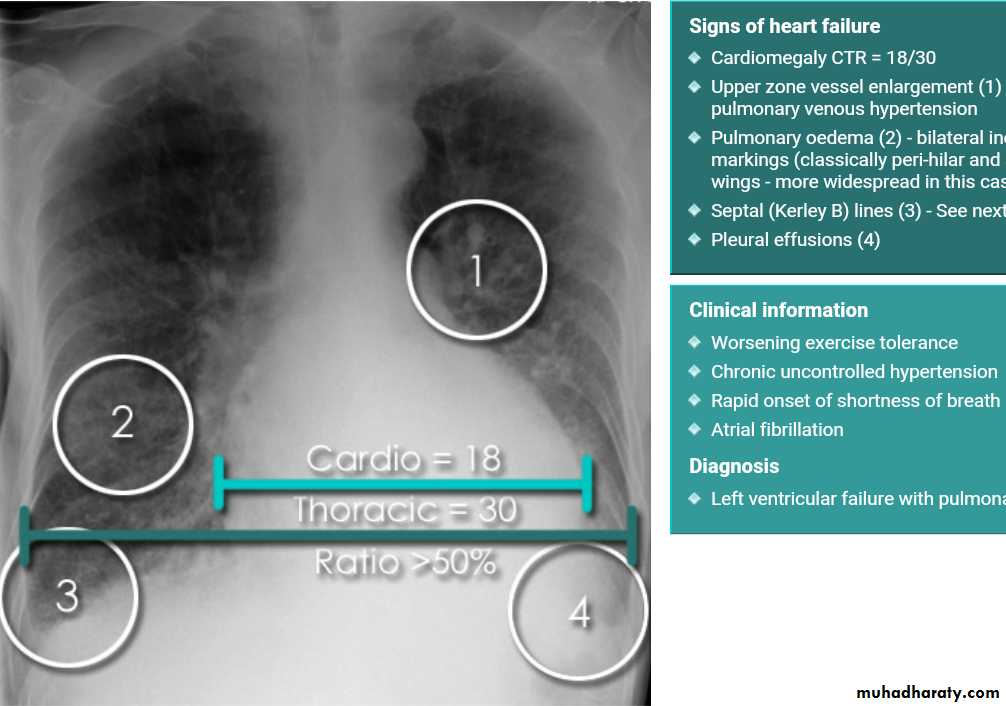

Cardiothoracic ratio (CTR) = Cardiac Width : Thoracic Width

A CTR of greater than 1:2 (50%) is considered abnormal. This however, assumes the projection is Posterior-Anterior (PA), and that cardiac size is not exaggerated by factors such as patient rotation or an incomplete breath in .

The cardiothoracic ratio aids in the detection of cardiomegaly, or more broadly,enlargement of the cardiac silhouette. .

Enlargement of the cardiac silhouette on chest x-ray can be due to a number of causes :

cardiomegaly (most common cause by far)pericardial effusion

With left sided congestive cardiac failure, the features are that of pulmonary edema which includes:

central pulmonary venous congestion ( prominent hilum )

cephalisation of pulmonary veins ( upper lobe pulmonary venous diversion )

pulmonary interstitial oedema

pulmonary alveolar oedema

Cardiomegaly

Pleural effusion

Septal lines, also known as Kerley lines, are seen when the interlobular septa in the pulmonary interstitium become prominent. This may be because of lymphatic engorgement or edema of the connective tissues of the interlobular septa. They usually occur when pulmonary capillary wedge pressures reach 20-25 mmHg ,

Kerley A linesThese are 2-6 cm long oblique lines that are <1 mm thick and course towards the hila. They represent thickening of the interlobular septa

Kerley B lines

These are 1-2 cm thin lines in the peripheries of the lung. They are perpendicular to and extend out to the pleural surface . They represent thickened sub pleural interlobular septa and are usually seen at the lung bases.